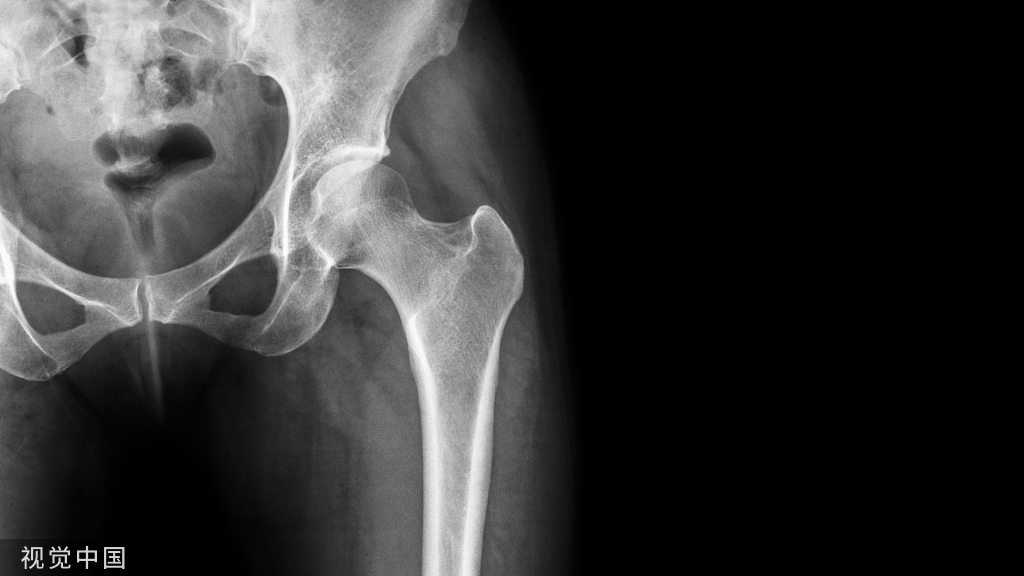

下肢牵引术

下肢牵引术应用比较广泛,从股骨颈骨折,转子间骨折,股骨骨折,到胫腓骨骨折等,都需要用到牵引。对于下肢骨折,两种牵引方法均可应用:皮牵引用于临时固定或术前稳定;而骨牵引多用于手术禁忌患者的治疗性措施。

Buck's(图 7)或 Russell's(图 8)皮肤牵引:在股骨骨折,转子间骨折或髋部骨折中应用广泛,下肢骨折使用皮牵引一般不能达到复位效果,但是可以在一定程度上减轻疼痛和保持局部肢体长度。

除此之外,在严重髋臼骨折股骨头中央型脱位患者中,可以沿股骨颈轴线方向进行牵引,减少股骨头髋臼中央的压力,并尽量获得一定程度上复位(图 13)。